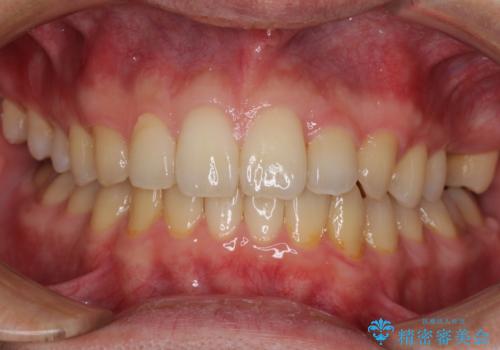

前歯のクロスバイトと抜歯が必要な奥歯の虫歯 インビザラインとインプラント治療

- 前歯のクロスバイトと、大学生のころから放置している虫歯を気にして来院された患者様です。

マウスピースでの矯正治療を希望されていましたが、前歯のクロスバイトは不十分な仕上がりや歯髄壊死などのリスクが高くなるため、術前にワイヤーで大まかに整えてからインビザラインにて矯正治療を行うこととしました。